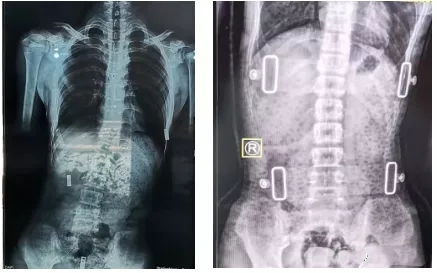

脊柱側彎支具的復查

一般我們認為����,支具治療3個月后需要進行復查。復查時需要脊柱全長正側位X線片�,同時觀察患者支具佩帶區(qū)域皮膚情況�����。治療過程中如果患者因生長發(fā)育或其他原因造成支具佩戴有不舒服的感覺��,需要重新制作支具��。支具一般需要持續(xù)佩戴至生長發(fā)育停止���,時間隨孩子就診時間以及生長發(fā)育狀況有所不同���。

有時戴了支具后脊柱會反方向傾斜。其實�,這是因為一般支具治療會采取一種“過度矯正”的方式�����,以保證脫下支具后身體的反彈更接近于中心線��,而不是向原側彎方向加重。